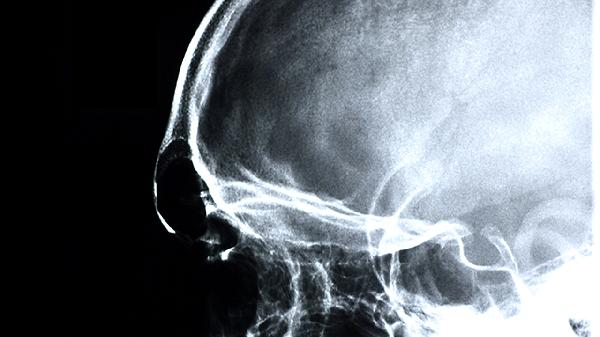

左脑暂时疼痛是怎么回事?

左脑暂时疼痛可能由偏头痛、紧张性头痛、颈椎病、高血压、脑供血不足等原因引起,可通过休息调整、药物治疗、物理治疗等方式缓解。